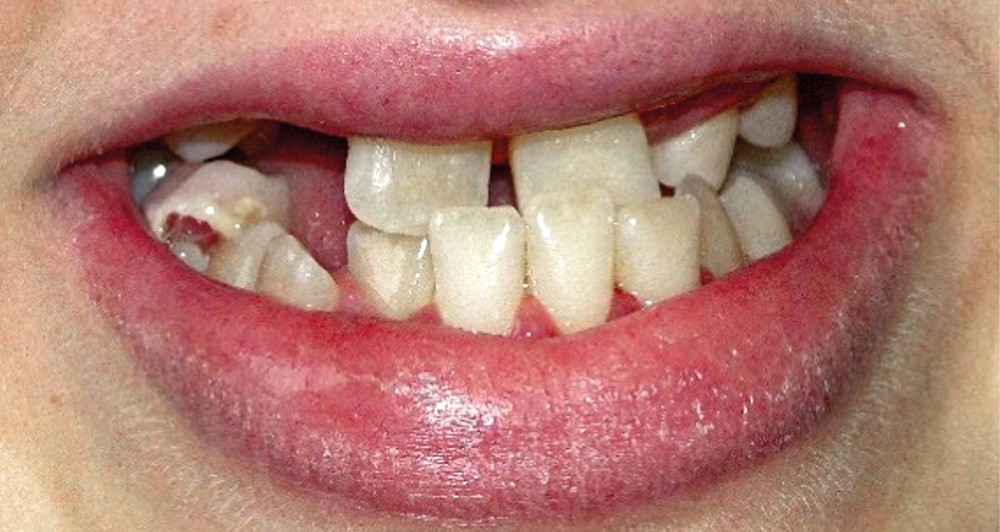

Au niveau exo-buccal, une classe III squelettique par brachymaxillie séquellaire est observée. L’hypodéveloppement de l’étage moyen de la face est l’une des conséquences de la radiothérapie reçue par la patiente dans sa jeunesse (fig. 2a à d) [4].

Au niveau endo-buccal, une mobilité des dents maxillaires, en particulier des incisives centrales (11 et 21), est remarquée. Elle peut s’expliquer par les séquelles dentaires du traitement par radio-chimiothérapie, bien visibles sur la radiographie panoramique (fig. 3). Au maxillaire…